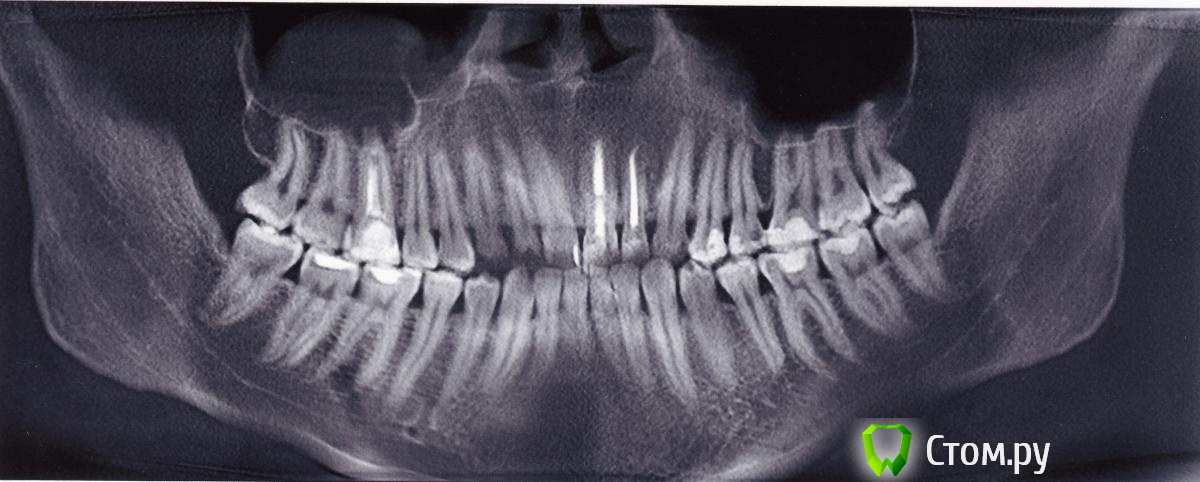

alessandor Опубликовано 8 июля, 2014 Поделиться Опубликовано 8 июля, 2014 Здравствуйте! Очень необходима Ваша консультация. Три недели назад после переутомления и переохлаждения распухла щека, никаких особых болей небыло. Сходил к стоматологу сделали снимок и компьютерное сканирование (КТ). Обнаружено обазование на корне 6 верхнего правого зуба (на снимке третий слева верхний зуб) и в гайморовой пазухе над ним. В 2009 был удален нерв и плохо запломбирован канал. Периодически последнее время при насморке была слабая ноющая боль, а незадолго до опухоли пульсация. Каких либо истечений из носа и насморка небыло, и нет сейчас. Стал принимать антибиотики - опухоль спала, через несколько дней после окончания приема щека снова распухла (может надуло в машине). Сейчас снова принимаю антибиотики (сегодня последний день) - опухоль снова спала. Все это время нос промываю долфином - что заливаю тоже и выходит (чисто). Зуб не шатается, не выпирает, при накусывании не болит (на всякий случай ем на другую сторону). Мне предлагают удаление зуба (говорят будет перфорация) со вскрытием гайморовой пазухи и удалением поврежденной слизистой оболочки. Другие предлагают попробовать полечить. При этом никто никаких гарантий не дает - как получиться. Конечно хочется сохранить зуб и не вскрывать гайморовую пазуху которая меня не беспокоит.Посоветуйте, очень на Вас надеюсь, как поступить, куда обратиться (готов приехать в другой регион), делать надо срочно, опасаюсь что снова распухнет. Могу дополнительно прислать и другие снимки из КТ. Заранее благодарю за ответ! С уважением, Александр. Ссылка на комментарий

dr-krasnov Опубликовано 8 июля, 2014 Поделиться Опубликовано 8 июля, 2014 Картина хронического правостороннего одонтогенного синусита, периапикального абсцесса в области 16 зуба. Показано хирургическое лечение и консультация ЛОР врача. 2 Ссылка на комментарий